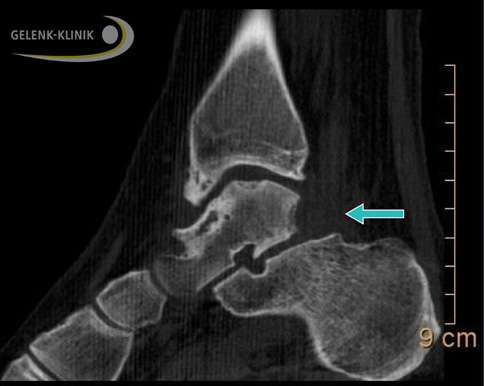

Fibulocalcaneares Impingement: Das Röntgenbild zeigt eine Einklemmung im oberen Sprunggelenk zwischen Wadenbein (Fibula) und Fersenbein (Calcaneus). © Gelenk-Klinik

Fibulocalcaneares Impingement: Bei dieser Form des Sprunggelenk-Impingements verspürt der Patient bei der Abrollbewegung des Fußes oder beim Gehen auf der Außenseite Beschwerden und heftige Schmerzen. Diese Schmerzen sind vor dem äußeren Sprunggelenk (Knöchel) oder unter dem Außenknöchel lokalisiert.